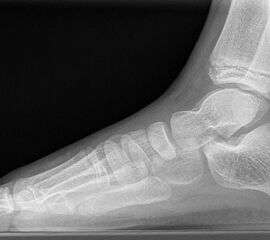

Standard ist die belastete Röntgenaufnahme des Fußes dorso-plantar und seitlich. Günstig ist eine Röhrenkippung von 10°-20°, um die Gelenke der Lisfranc-Linie einsehen zu können.

Ergänzend kann eine Schrägaufnahme hilfreich sein. Bei Metatarsalgien oder Pathologien der Sesambeine liefert die Sprinteraufnahme zusätzliche Informationen. Bei einer Pes planovalgus Fehlstellung wird ergänzend ein Saltzman view durchgeführt.